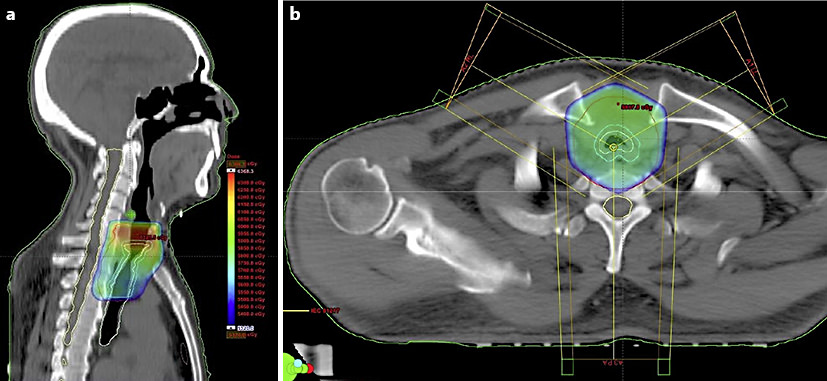

mHCC Survivor

NA